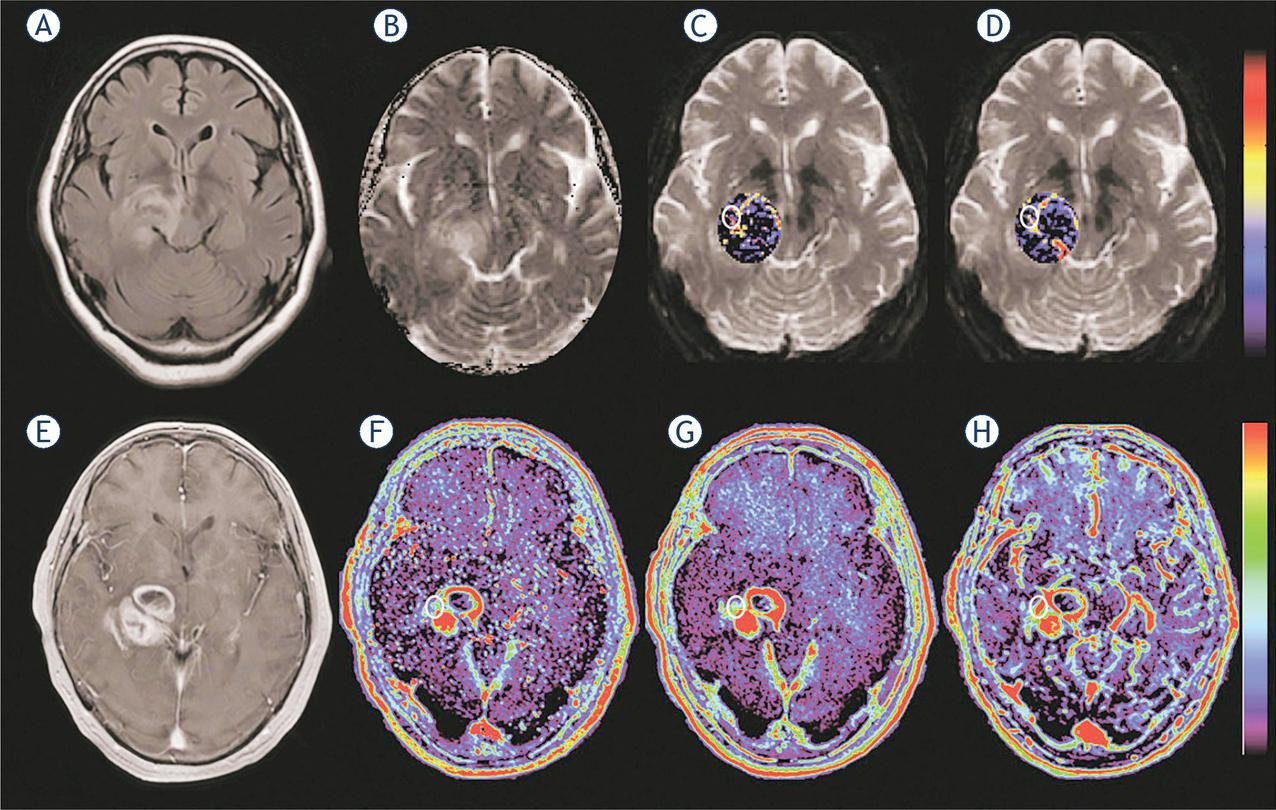

Figure 2